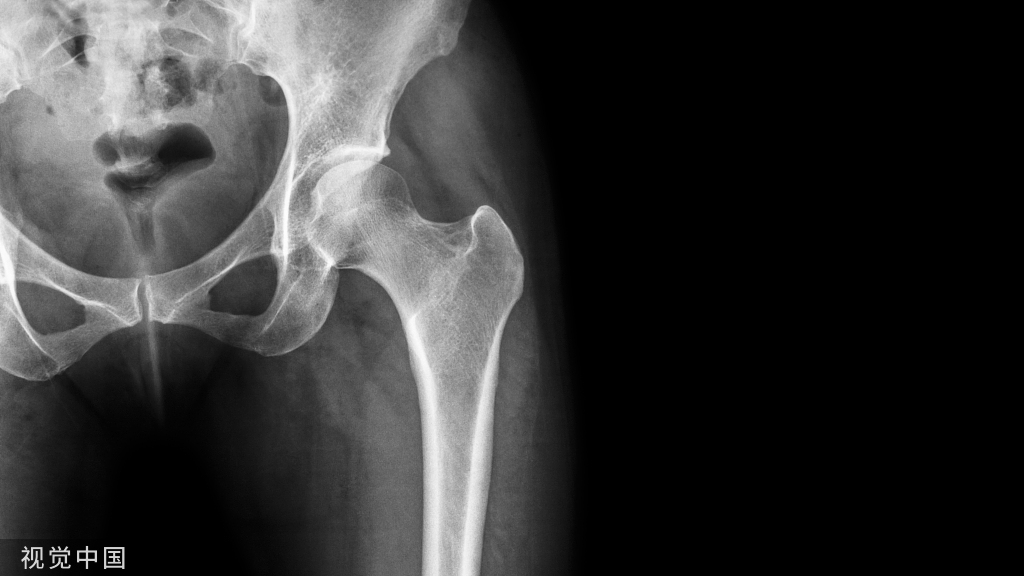

内踝垂直型骨折的手术技巧!

复位内踝骨折块之前,需仔细清理骨折端。关节面如存在塌陷,可翻书样将内踝骨折块掀开,暴露并复位关节面、植骨。

两枚克氏针临时固定,在关节线上方 1 cm 水平进针,一前一后,尽量靠前靠后,为钢板置于两枚克氏针之间预留空间。

4 孔 1/3 管型钢板,骨折线远近端各两孔,近端采用皮质骨螺钉双皮质固定,注意第 2 枚螺钉应位于骨折线近端 3 mm 处。远端采用 4 mm 部分螺钉松质骨螺钉固定。